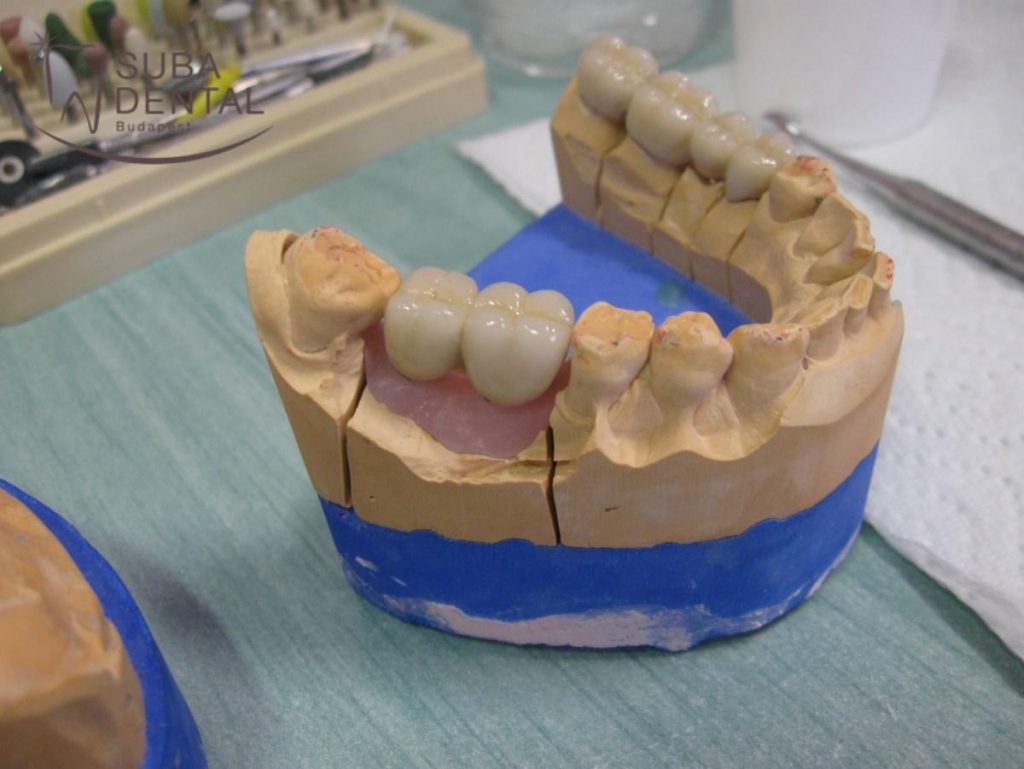

A lenyomatvételek után több próbafázist kell elvégeznünk, ahogy a fogtechnikus halad a koronák elkészítésével. A vázpróba során ellenőrizzük, hogy pontosak voltak-e a lenyomatok, precízen készült-e el a fogpótlás váza, illetve minden fogpótlásnak tökéletesen kell illeszkednie a mestermintán. Itt ellenőrizzük még a harapást, a váz hosszát, azt, hogy elég hosszúak-e a fogak, középen van-e a 2 nagymetsző, illetve hogy szép ívben haladnak-e a fogak hátrafelé. A nyerspróbán a koronák már szinte készen vannak, a fém vázra már rá van leplezve a kerámia. Ezen a próbán még jobban ellenőrizhető a páciens harapása (funkció) valamint a koronák alakja, színe, a középvonal és a mosolyvonal (esztétika próba). A különböző próbák között több nap is eltelik, ilyenkor a háttérben a fogtechnikusok dolgoznak a fogpótláson. A próbák közötti időben megtörténik a szükséges fogak gyökérkezelése és újra gyökérkezelése is.

Alsó fémkerámia koronák saját fogakra és ragasztható implantátum koronák gipszmintán

Felső fémkerámia körhíd gipszmintán